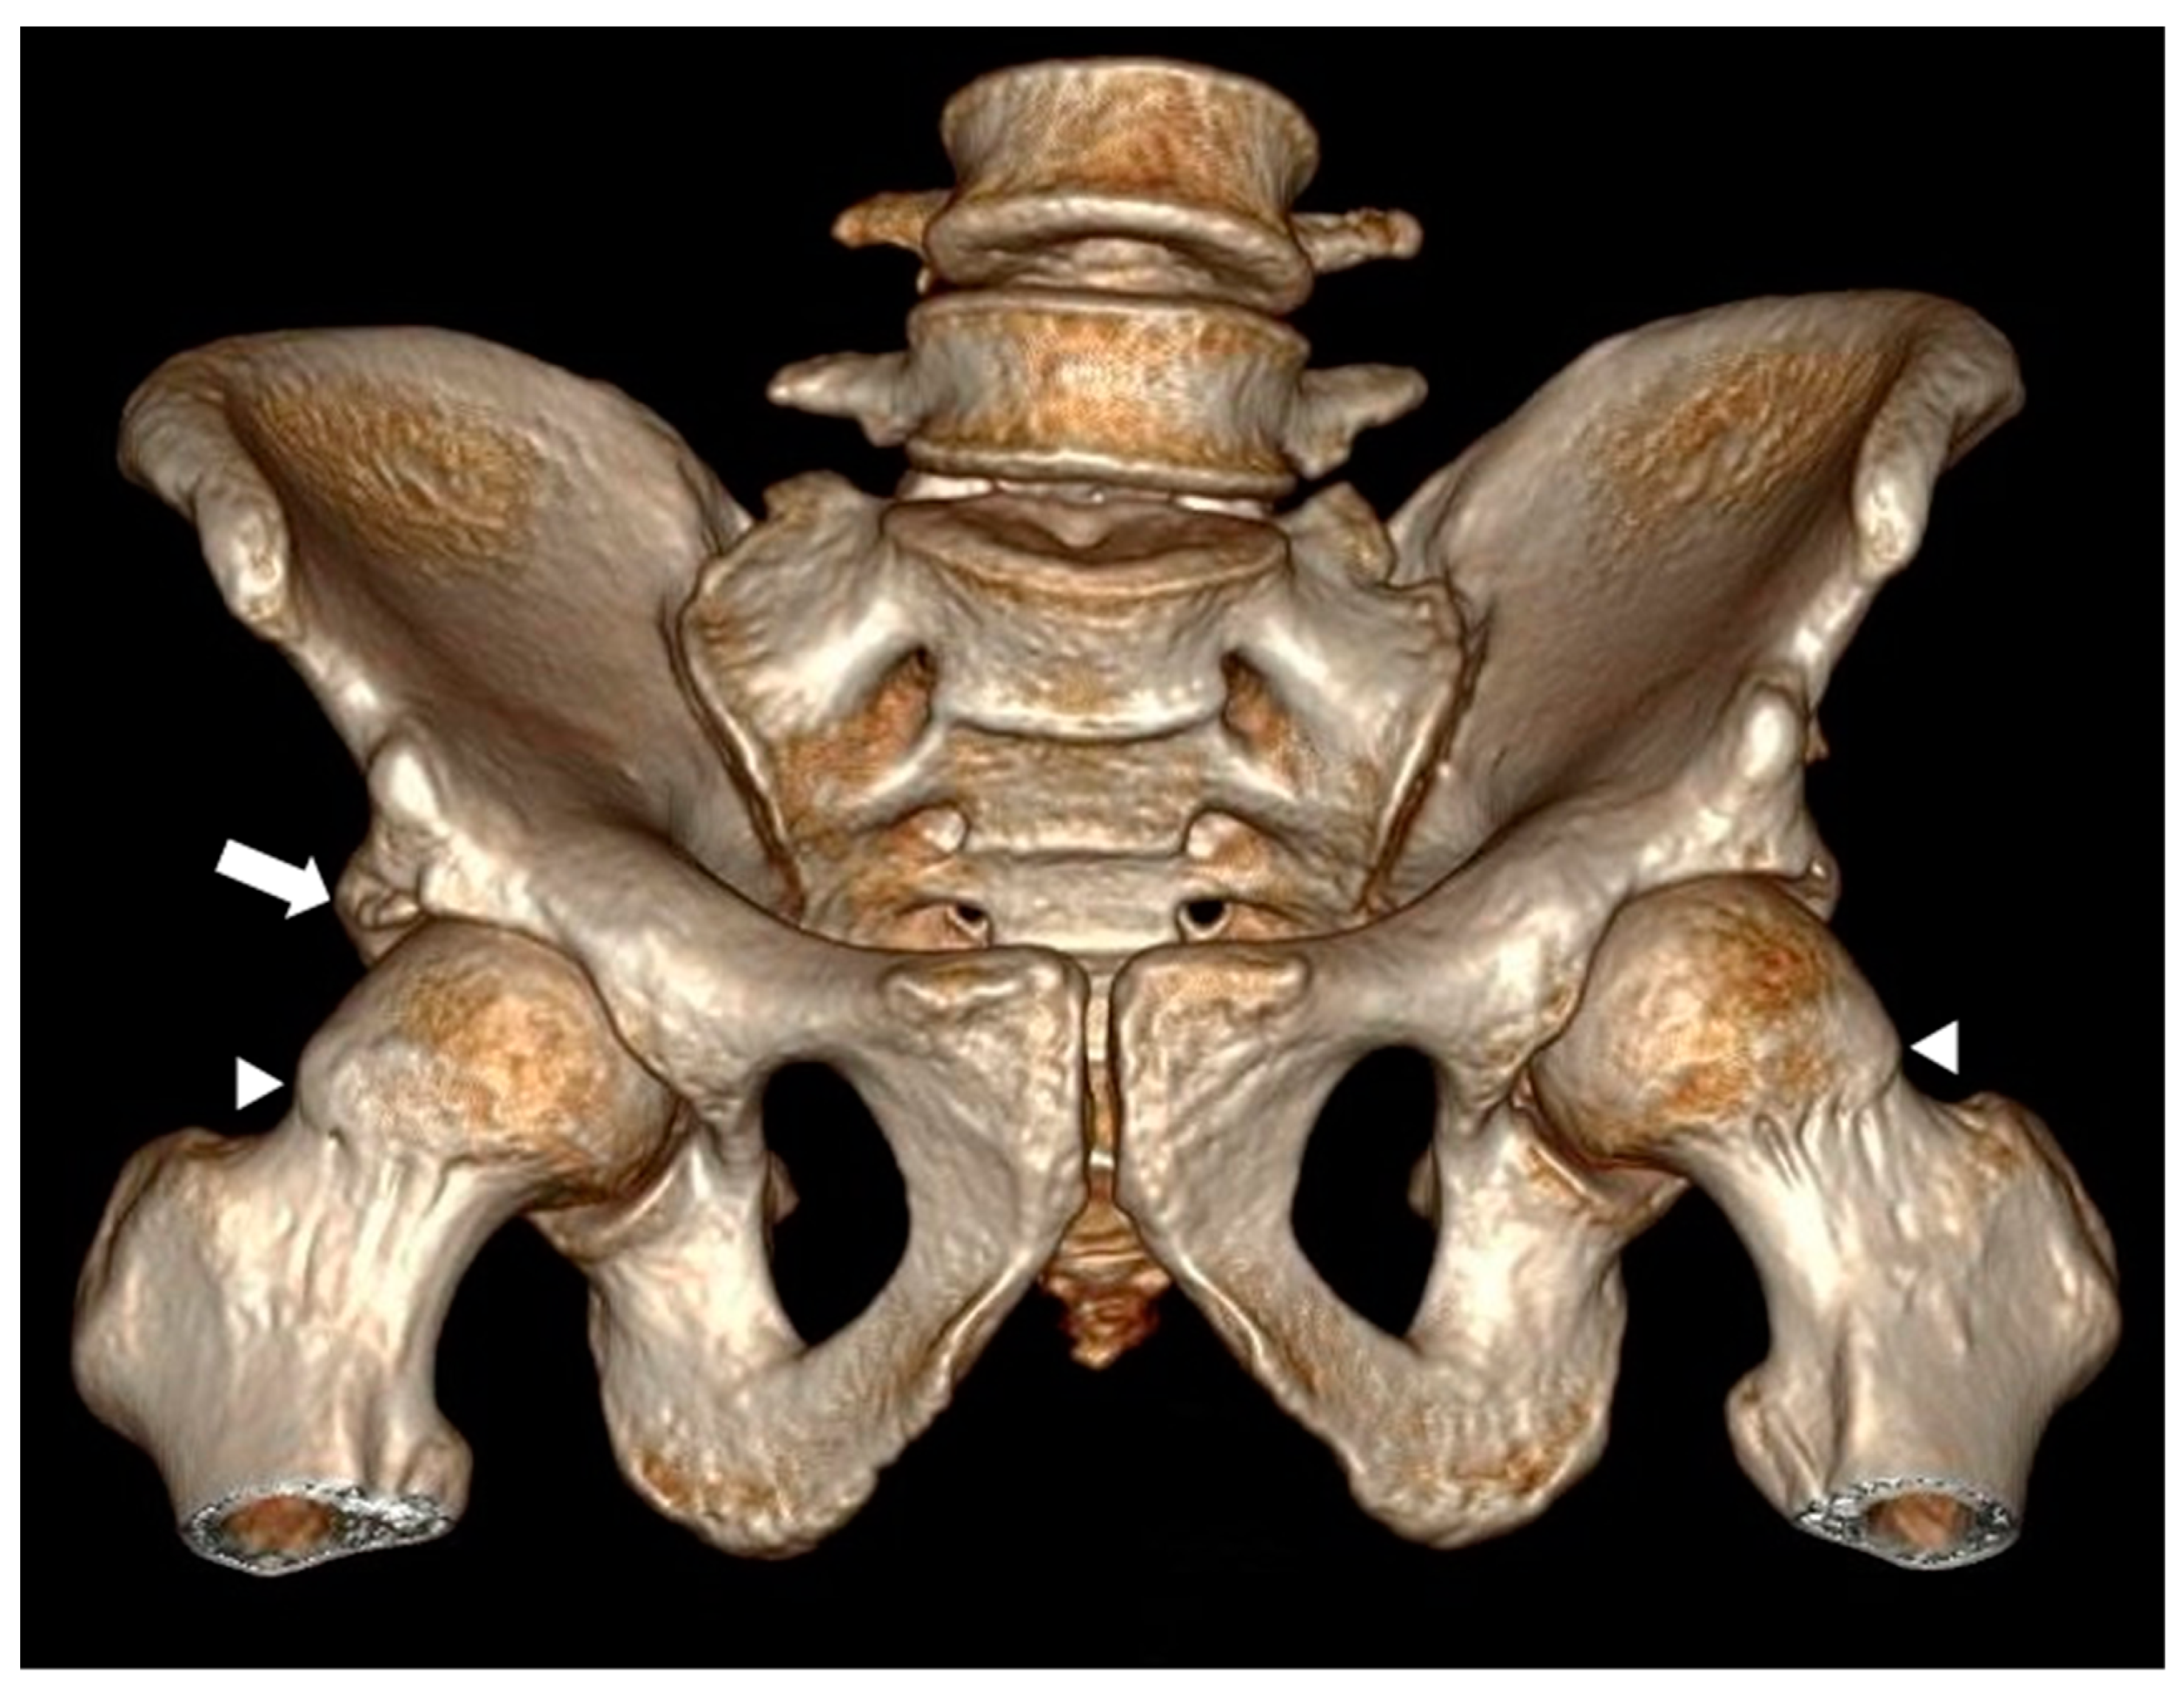

The anthropometric data revealed a general average height of 1.53 m and weight of 68.26 kg (SD ± 14.3). With respect to BMI, the mean was 29 (SD ± 14.3). Of the total patients, 47% presented morphological changes in femoroacetabular impingement, of which 37 correspond to the pincer-type, 17 to the cam-type, and 7 to the mixed-type (an example of mixed-type is shown in Figure 1).

Figure 1.

Computed tomography image with 3D volumetric reconstruction showing anterosuperior bony prominence in the cervical–cephalic transition of the bilateral femur, as well as bone excrescence in the right acetabular roof. Findings in relation to right mixed-type and left cam-type femoroacetabular impingement are marked with white arrowheads.